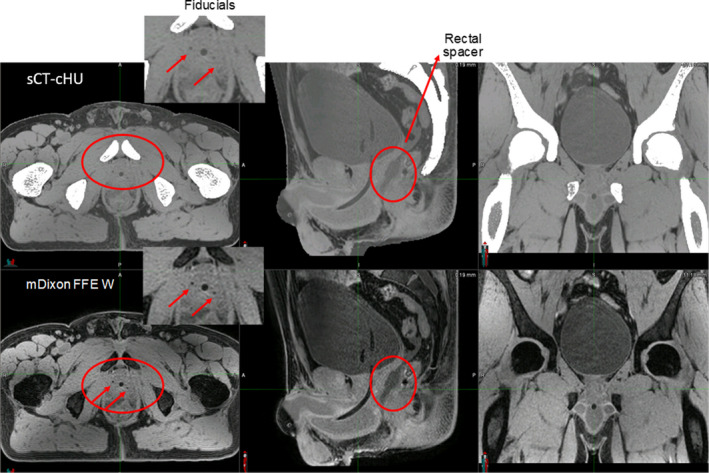

Large FOV acquisition is challenging in terms of geometric accuracy in the SI direction. Two‐stack mDixon acquisition mitigated that. Large FOV did not show any image inhomogeneity or fat‐water swap artifact based on visual inspection. Continuous HUs provided soft tissue and bone contrast on the sCT that is comparable to CT. Fiducials and Foley catheter were visible as dark signal on the sCT. Even rectal spacer showed a slightly darker contrast on sCT compared with nearby soft tissue as shown in Fig. 3. Spacer is typically not seen on the CT. sCTs reconstructed successfully in both prone and supine positions as well as a slightly frog‐legged position used for gynecological setups.

FIG. 3.

Soft tissue visibility on continuous HU synthetic CT as well as source MRI (mDIXON FFE Water). Images were acquired with 3T field strength (HU: Hounsfield unit, CT: computed tomography, MRI: magnetic resonance imaging, FFE: fast‐field echo, A: anterior, P: posterior, S: superior, I: inferior).

In a multi‐institutional study setting, we investigated the soft tissue visualization, dosimetric accuracy, and tissue‐specific HU similarity of a commercially available sCT‐cHU approach, MRCAT general pelvis. Our analysis suggest that this approach provided soft tissue and bone contrast on the sCT that is comparable to CT. Two‐stack acquisition enabled geometrically accurate MR as well as synthetic CT images and allowed anatomic coverage up to L1–L3 vertebrae to enable treatment of superior nodes including para‐aortic nodes. sCTs reconstructed successfully in both prone and supine positions as well as slight frog‐legged position used for gynecological setups. Soft tissue visualization scoring demonstrated high confidence in bladder, mesorectum and prostate rectum interfaces. All soft tissue visibility was substantially improved from the widely utilized prostate only sCT‐BD approach, as demonstrated in Fig. 2. In prostate cases, the rectal spacer showing as darker contrast compared with prostate and rectum allows for improved prostate and rectum boundary delineation when compared with CT. This has huge implication for CT‐cone‐beam computed tomography (CBCT) alignment on a linac where the spacer on the CT can only be displayed by the spacer contour. Even though fiducial visualization results were less consistent among the study cohort, it is a large improvement compared with the widely utilized bulk density approach in which fiducials are barely visible in the sCT.